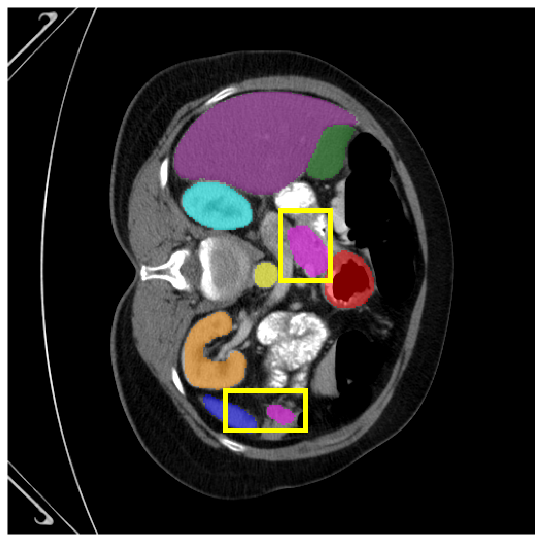

4.3.2 Visual Comparisons

Visualization of our method on the Synapse and ACDC datasets is shown in Fig. 3(a) and Fig. 3(b). For the Synapse dataset illustrated in Fig. 3(a), FCT failed to accurately segment SM and GB, while MERIT achieved precise segmentation of SM but struggled with GB. In contrast, our method achieved accurate segmentation of both SM and GB. Regarding the ACDC dataset shown in Fig. 3(b), while previous methods achieve comparable segmentation of the Myo and LV to the GT, they exhibit noticeable errors on the RV, including invasion into adjacent organs and misrecognition. On the other hand, our method accurately segments across all three structures Myo, LV, and RV, performing as precisely as the GT. We demonstrate the superiority of our method quantitatively and qualitatively.